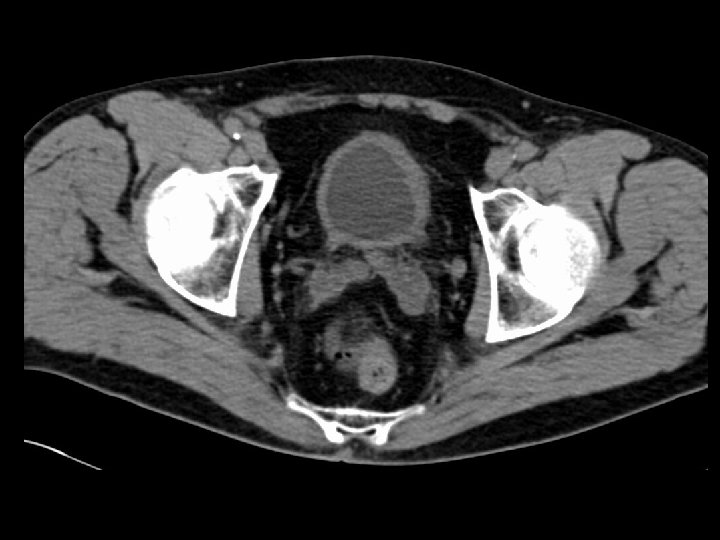

Adrenal macronodular hyperplasia • Findings: – Bilateral lobular enlargement of the adrenal glands. • ddx: – Cushing’s syndrome – Metastases – Infection • Tuberculosis • Histoplasmosis